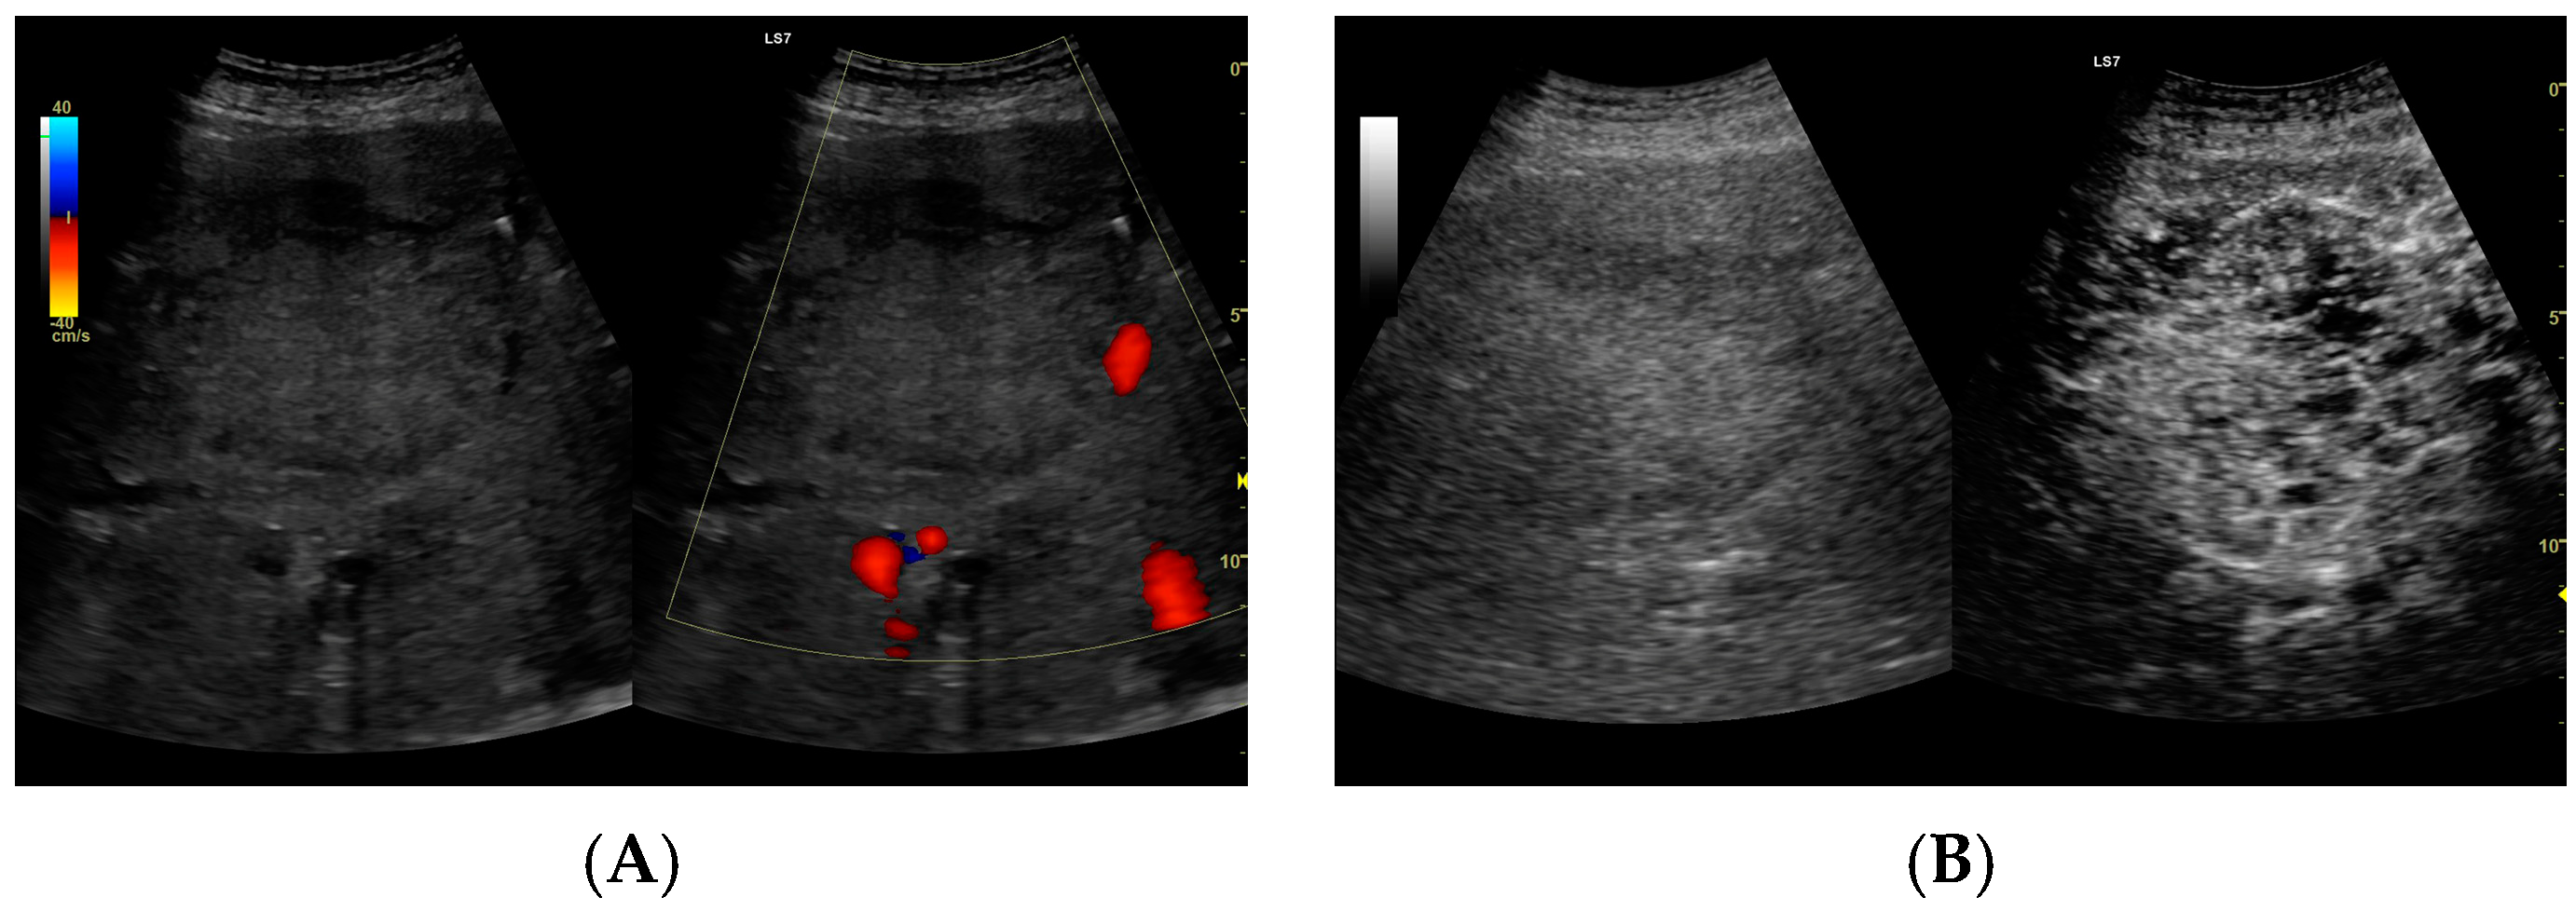

Figure 4.

(A) Ultrasound and color Doppler: The transverse view shows a focal lesion in the right liver lobe, identified as type II—honeycomb. In B-mode, the lesion appears solid and heterogeneous, surrounded by a hyperechoic capsule. Confident classification of the lesion as a hepatic abscess based on these images alone is impossible, including accurate determination of the content and location of the fluid component. (B) CEUS arterial phase: The enhanced abscess capsule is visible, with the lesion being heterogeneously contrasted and hyperdense in relation to the liver parenchyma. Hypodense fluid areas corresponding to pus are also visible. The total abscess was estimated to be 40.71 cm² from CEUS, while the fluid fractions were estimated at 0.44 cm² on B-mode and 6.17 cm² on CEUS, respectively, which, according to the methodology used, translates to 3.23 mL in B-mode and 45.35 mL in CEUS, respectively. The enhancement of the abscess capsule is similar to that of the parenchyma, and the greatest phase of inflammatory activity has passed, indicating that the lesion is in the resolution phase of inflammation.